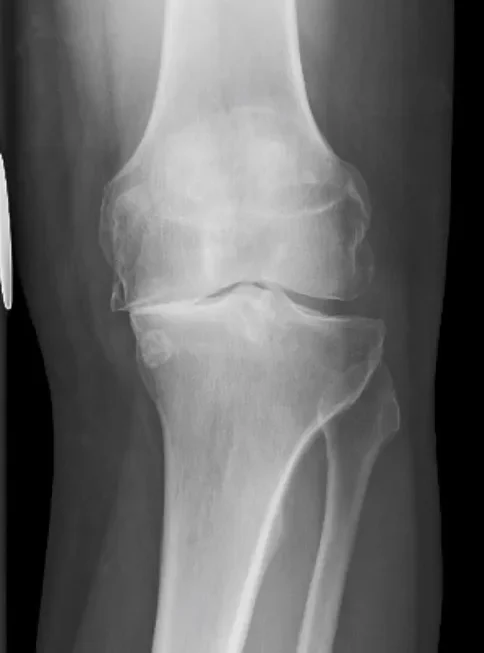

En la evaluación diagnóstica de la artrosis de rodilla, las radiografías convencionales siguen siendo el estudio de imagen más utilizado debido a su accesibilidad, bajo costo y capacidad para revelar cambios estructurales relevantes. Las proyecciones radiográficas más comúnmente recomendadas incluyen vistas posteroanteriores con apoyo de peso corporal y flexión de rodillas a cuarenta y cinco grados, además de proyecciones laterales y específicas de la articulación patelofemoral, como la vista de Merchant. Estas posiciones permiten una visualización más precisa de las distintas compartimentos de la rodilla, y favorecen la detección temprana de alteraciones estructurales que podrían pasar desapercibidas en proyecciones estándar.

La importancia de realizar radiografías con carga radica en que el peso corporal aplicado sobre la articulación simula las condiciones funcionales habituales, lo que permite evidenciar con mayor claridad la disminución del espacio articular provocada por la pérdida de cartílago hialino. Esta reducción del espacio interóseo es uno de los signos más característicos de la artrosis y refleja directamente el grado de desgaste cartilaginoso. A medida que la enfermedad progresa, pueden observarse otros hallazgos radiológicos típicos, como el aumento de la densidad ósea subcondral, conocido como esclerosis, que representa una respuesta del hueso a la sobrecarga mecánica crónica.

Asimismo, es común identificar la formación de osteofitos, que son proyecciones óseas anormales localizadas en los márgenes articulares. Estos crecimientos óseos representan un intento del organismo por estabilizar la articulación degenerada, aunque frecuentemente contribuyen a la limitación del movimiento y al dolor. También pueden observarse cambios quísticos en el hueso subcondral, conocidos como geodas, que son cavidades llenas de líquido sinovial y resultan del colapso de trabéculas óseas por microtraumatismos repetidos.